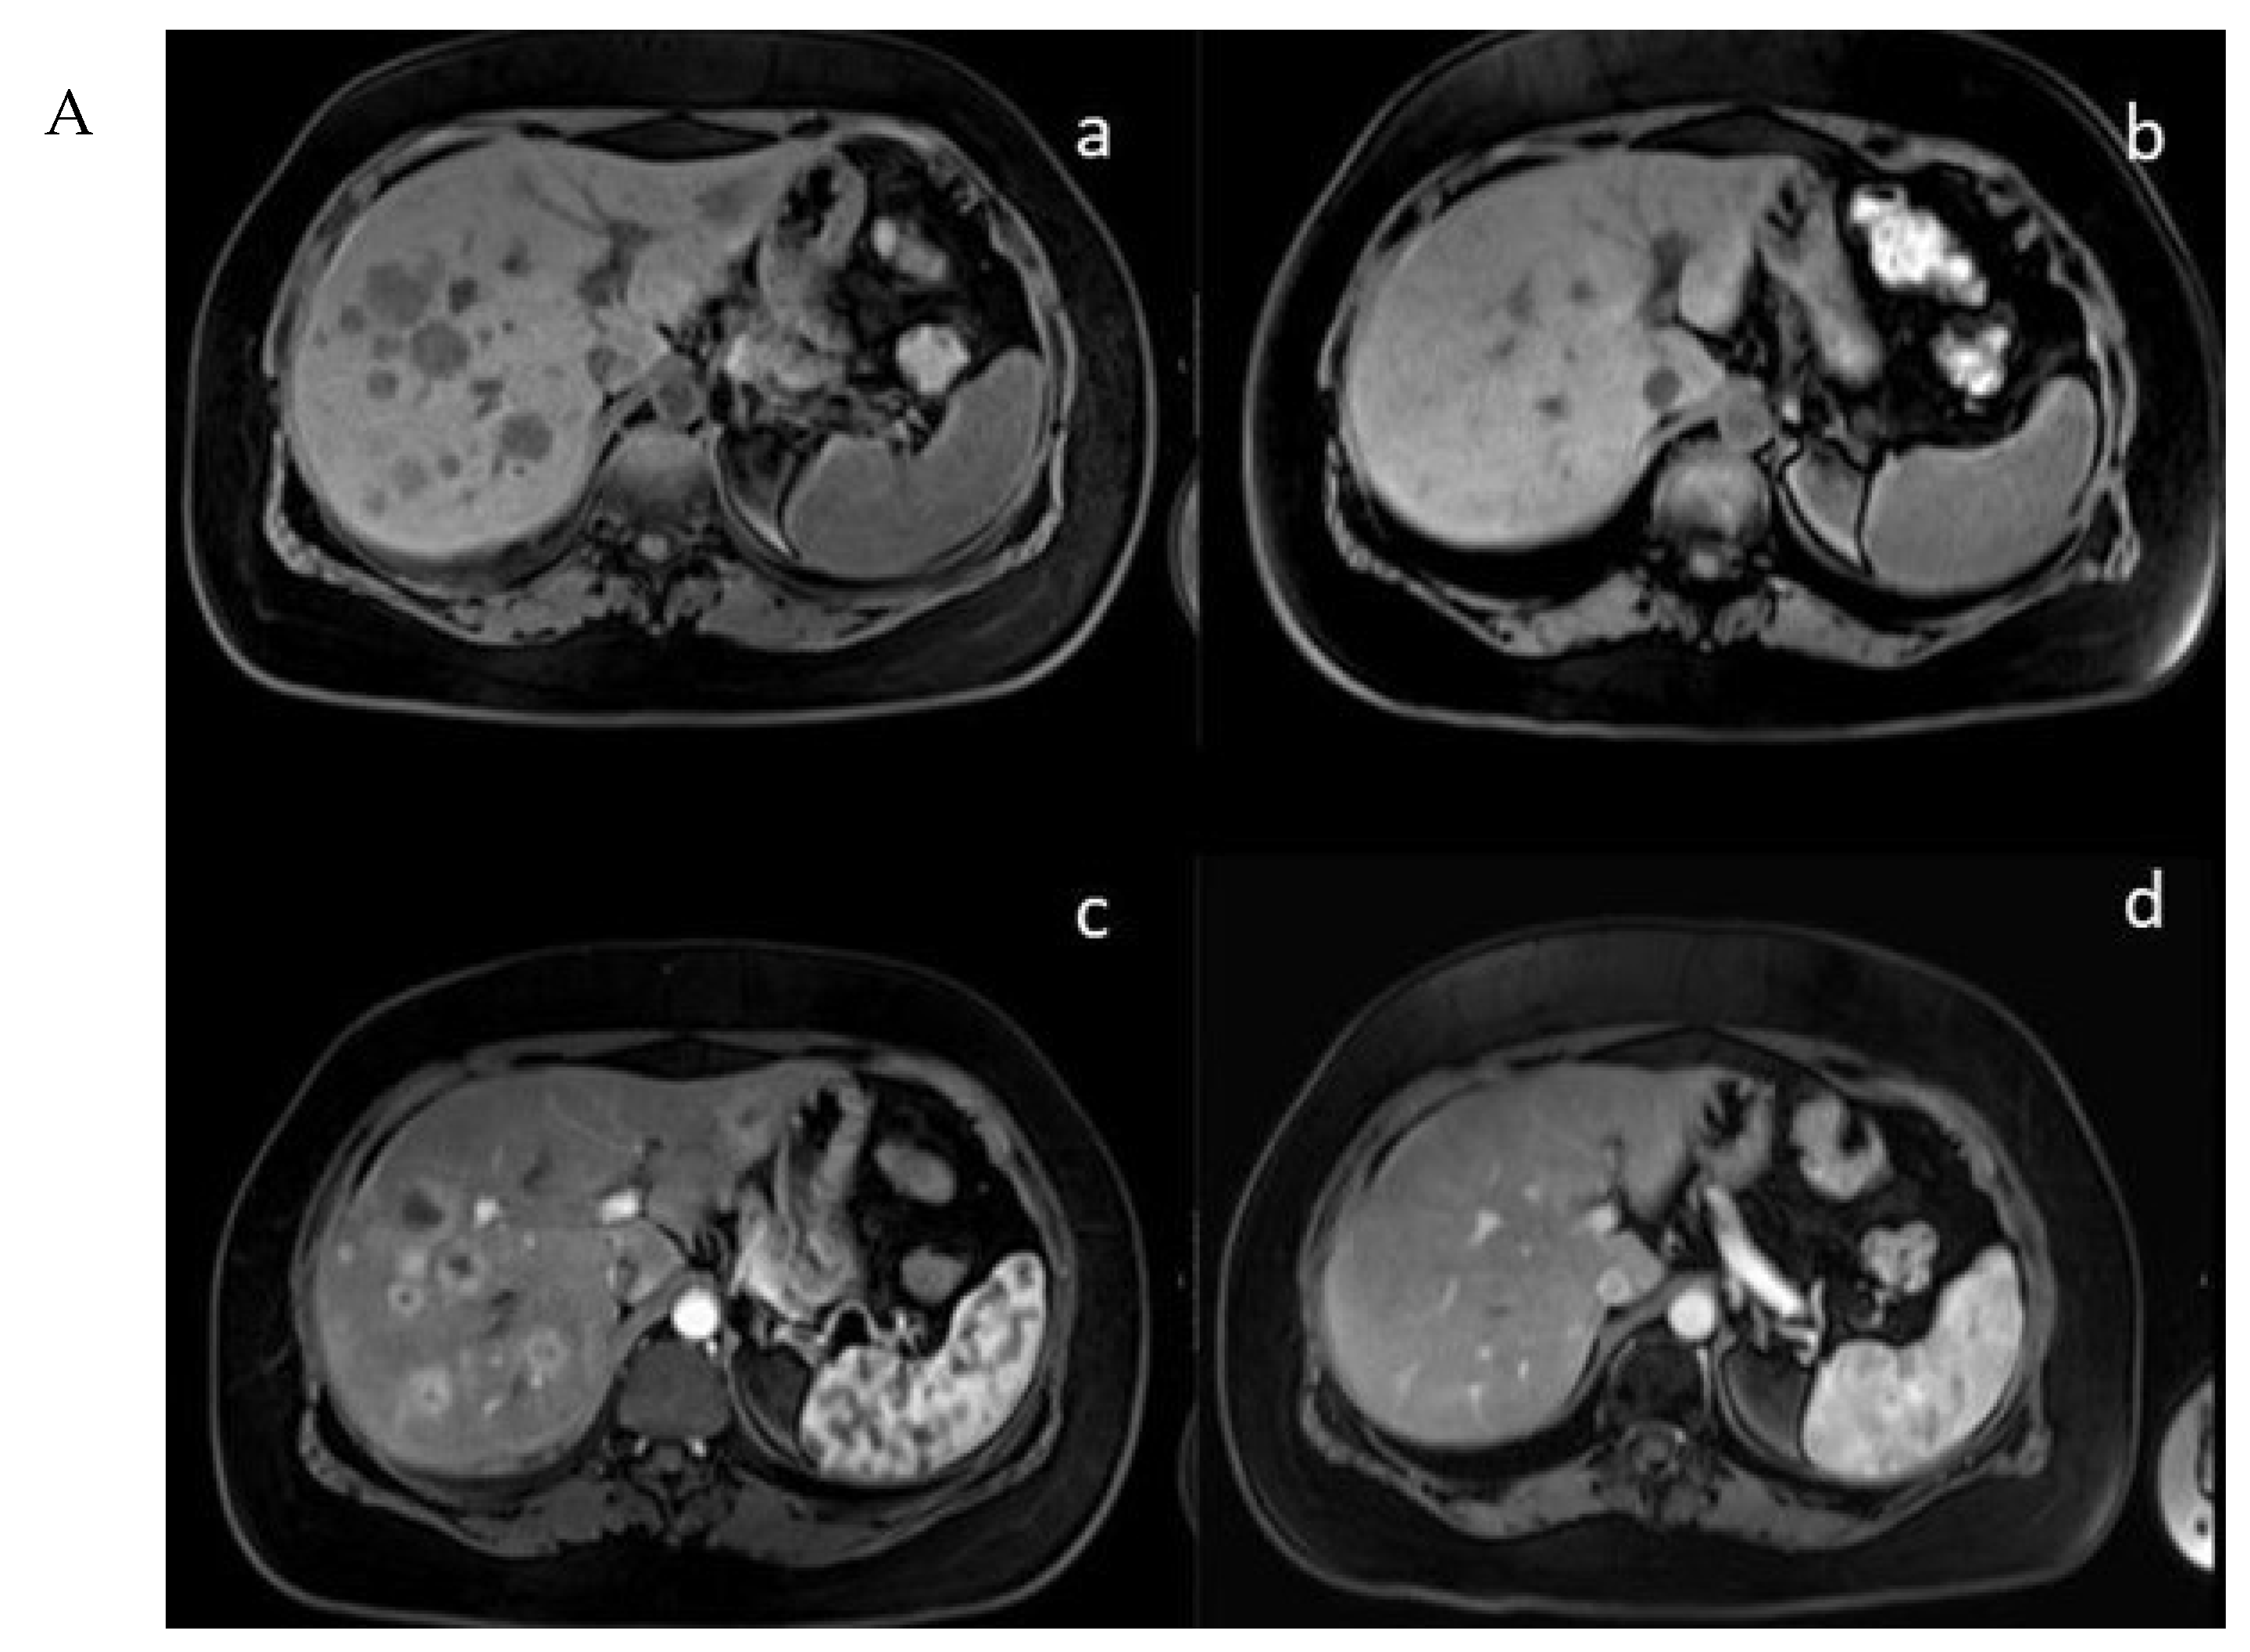

In the mTMZ + bevacizumab cohort of 30 patients, 4 (13.3%) exhibited a complete response (CR) (Figure 3), 15 (50.0%) demonstrated a partial response (PR), 7 (23.3%) had stable disease (SD), and 4 (13.3%) experienced progressive disease (PD). The overall objective response rate (ORR), combining CR and PR, reached 63.3% (19 patients), while the disease control rate (DCR), which includes CR, PR, and SD, stood at 86.7% (26 patients) (Table 2). In the course of our study evaluating the temozolomide–bevacizumab (mTMZ–bevacizumab) regimen for metastatic neuroendocrine tumors (NETs), treatment was continued until patients experienced intolerable side effects, disease progression, or death. Of the 30 patients included in our study, 18 patients reached mortality due to disease progression.

Figure 3.

(A) (upper) Downstaging tumors (complete response) after metronomic TMZ–bevacizumab combination therapy. MRI images for the patient with metastatic NET before (a,c) and six months after treatment (b,d); (B) (bottom) downstaging tumors (complete response) after metronomic TMZ–bevacizumab combination therapy. Gallium-68 (Ga-68)-DOTATATE positron emission tomography (PET) images for the patient with metastatic NET before (e,g) and one year after treatment (f,h).